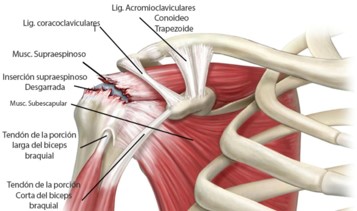

Desgarro del Manguito Rotador

El manguito de los rotadores esta constituido por 4 músculos que vienen de la escápula: Supraespinoso, Infraespinoso, Redondo menor y Subescapular. Los cuales son estabilizadores dinámicos de la articulación Glenohumeral.

Las lesiones del manguito de los rotadores son frecuentes y aumentan con la edad (desgarros degenerativos), pueden ocurrir como problema laboral por el movimiento repetitivo del miembro superior por encima de la cabeza, secundario a luxaciones de la articulación Gleno humeral.

Los desgarros dependiendo de sus características pueden ser tratados con fisioterapias, tratamiento quirúrgico artroscópico y en casos de ser irreparables se utilizan técnicas de trasferencia tendinosa o reemplazo articular.